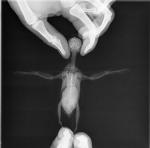

Ромашка :) Опубликовано 23 апреля, 2016 Автор #33 Опубликовано 23 апреля, 2016 Курита, Здесь на форуме прочла, что волнистых попугаев как вид полностью уже испортили, загубили. Очень много умирают от опухолей врач мне то же самое сказал.. Delfin, ольга 84, Курита, - Спасибо вам за поддержку! Delfin -дай бог выжить... врач сказал - не выживет... Посмотрите, какой Ромочка на рентгене

Ромашка :) Опубликовано 24 апреля, 2016 Автор #34 Опубликовано 24 апреля, 2016 (изменено) Были у врача Томашевского Александра в Белый Клык. Осмотрев птицу Александр сразу сказал- опухоль семенника, предложил не делать рентген, т.к. дорого и нет смысла, но я бы потом всё время думала, а вдруг..? и поэтому решила рентген сделать. Рентген подтвердил диагноз. Назначили антибиотик и обезболивающее. Сколько Роме осталось я не спрашивала, не могу... Александр сказал- если будет совсем плохо, усыпить.. Я умом всё понимаю, сердцем нет В нашем случае действительно НУЖНО БЫЛО СРАЗУ ПОЙТИ К ВРАЧУ!! По крайней мере я бы не потратила 2000 на анализы, нам анализы оказались не нужны..... Пушистик просит есть, но кашу не ест и всё! Опять кормила через зонд- если орёт с зондом во рту, это я правильно попала? В первый раз обратно пошла каша с непереваренными зёрнами , много дала? ( страшно, а что делать..)Неперевареные зёрна в 12 ночи??? Поел в 3 дня и почему не переваривается?? Теперь только мягкий корм, у Ромы опустился желудок вниз и сдавлен опухолью, поэтому мало какает. Скажите, от мягкого корма понос это нормально? ОЧЕНЬ помогла эта ссылка *Кормление Через Зонд КОРМЛЕНИЕ ЧЕРЕЗ ЗОНДи тема DelfinКстати, спрашивала зонд 18 сказали нет, потом нашли такой, девушка не могла на нём № найти, мелко в уголке написано 21G Кормлю кашей Помогайка от Нестле, написано там пробиотики и пребиотики, дополнительно нужно что-нибудь? А попугай чувствует сытость при кормлении через зонд?? Изменено 24 апреля, 2016 пользователем Ромашка :)

Delfin Опубликовано 24 апреля, 2016 #35 Опубликовано 24 апреля, 2016 увы, ренгены читать не умею, могу только явные траблы с костями еще глянуть.... ГКС назначили для уменшения опухоли? - если выписали только обезбал и антиб - стучитесь к Зосе и просите лечение от опухоли. Да, шансы мизерные, НО: можно продлить птице жизнь без боли.Если орет с зондом - то правильно, зонд в пищеводе. Если пошла рвота едой при зондировании -это значит птиц поел перед этим -и понятно что рвотный рефлекс получился -птицу вырвало. ЛИБО зоб был полный, и вы еще зондом накормили -поэтому всегда проверять зоб на ощупь!!От мягкой еды, каш конечно же будет светлый и жидкий помет. Я уже привыкла про номера катетером - както тут сравнили по диаметру катетеры разных номеров - оказалось ТРУБКА везде одна и та же, отличаются лиш диаметром самой ИГЛЫ.Про кашу - лучше взять кашу для ручного вскармливания птенцов попугаев Нутриберд - там уже все есть что нужно. Если берете детские безмолочки или сами делаете -то я добавляю пробиотик, карсил (у нас с вами печень увеличина), ферменты поджелудочной, нистатин (если даете антибиотик, да и вообще - прикормлении зондом есть риск получить кандидоз)Про сытость через зонд - не могу сказать... порой он сразу идет спать, а порой после зонда бежит еще немного зерна поклюет (я никогда зоб до отказа не набиваю, даю по 1,5-2 мл)